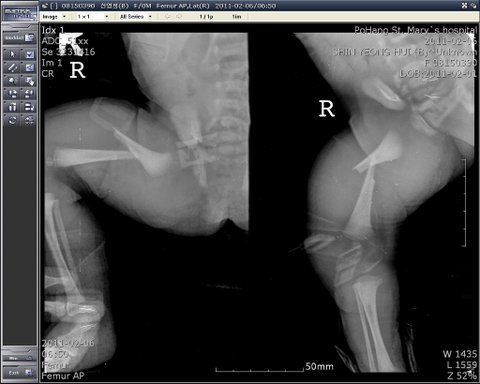

(애기 엑스레이 사진과 소아과원장과 얘기를 나놨습니다.이때 애기과 왜 이렇게

되엇냐고 묻자 잘모르겠다며 당황 했었고 (추후cctv확인결과 엑스레이 사진은 1시

56분경에 찍으러 내려가는것 확인함)

우리는 담담여의사에게 다리가 왜 골절이 되었는지에대해서 몇차례 물었으나  담당여의사는

다리골절에 대해서 설명을 계속 못했고 위 질문에 대한 얘기는 안하고 다른 얘기만 늘어놨습니다.

그리고 난뒤 대표원장및 담당간호사와 같이 면담할때 대표원장이 수술과정에서 골절이 된거같다 라는

말을 처음 하였습니다. 담당 간호사는  기저귀를 갈때 다리가 덜렁 덜렁거려서 다리안들고 골반을 손가락으로 들어서 갈았다고 했고, 다른 간호사는 애기 사진찍고 나서 목욕을 시켰다고 했습니다. 사진이라면,저희가 알고있는 사실이라면 출발 직전 찍은 엑스레이 사진이 전부인걸로 알고있습니다. 그렇다면 부러져 있는 상태에서 애기 목욕을 시켰다는 얘기입니다....

병원측에서 말한 수술할때 뼈가 골절이 되었다고 가정했을때 입니다.

1.  출산후 발도장을 찍을때 뼈가 골절이 된상태로 발도장을 찍었더라면 왜 확인이 안되었나?

2.  출산 직후 수술실 복도에서 담당의사와 제가 애기상태를 확인할때 별다른 특이사항이 없었느냐?

3. 애기가 출산후 신생아실에 갔을때 애기를 세척(목욕) 시킬때와 기저귀 교환할때 왜 몰랐는가?

4. 2011년 2월 1일날 오후 12시 30분경 산모와 친할머니가 애기 것싸게 벗기고 확인할때 왜 이상없다고

간호사가 얘기햇는가?

차트상에는 오전 11시에 대퇴가 심하게 부어있었다고 되어있는데 산모와 친할머니가 애기상태확인한

시간이 12시 30분경이였습니다. 그럼 왜 저희가 애기 확인하러 갔을당시 왜 저희에게 아무런 말이

없었을까요? 그리고 저희에게는 이상이 없다고 말했었습니다.)

만약 위 내용과 같이 출산할때 골절이 아니라면 신생아 실밖에 없는데 정작 중요한 신생아실 cctv는

없었습니다. cctv자체가 신생아실에는 없엇습니다. 이유인즉 건물 신축들어가기때문에 예비신생아실이므로

cctv가 없다는겁니다.